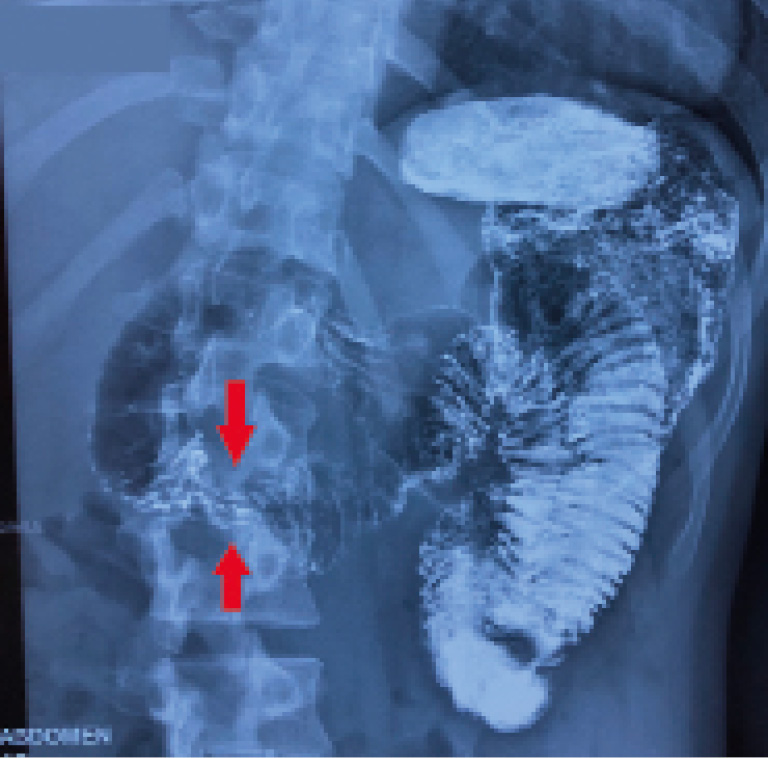

По данным рентгеноскопии с контрастированием имеются спастические проявления нисходящей части ДПК, стойкое сужение проксимального отдела горизонтальной ветви ДПК на протяжении 15–20 мм, маятникообразное движение контраста по нисходящей части в луковицу (рис. 3).

Рис. 3. Рентгеноскопическая картина аортомезентериальной компрессии (маркирована зона сужения горизонтальной ветви ДПК)